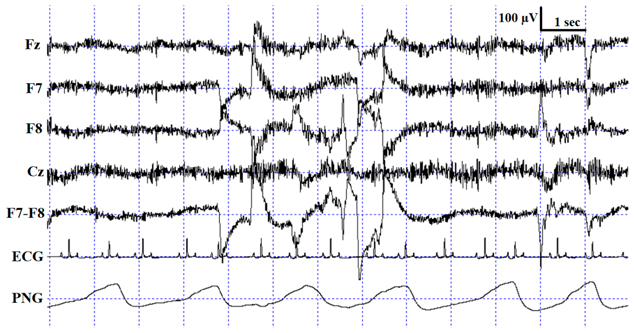

Table 1.

Description of the applied scoring criteria and characteristic polysomnographic view of sleep stages (EEG channel = Fz, F7, F8, Cz derivations; EOG (electrooculography) channel = F7−F8 derivations).